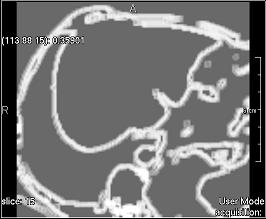

Contrast (simple)

../../../Modules/ML/MLFilter2/mhelp/Images/TextureFilterImages/contrast.jpg